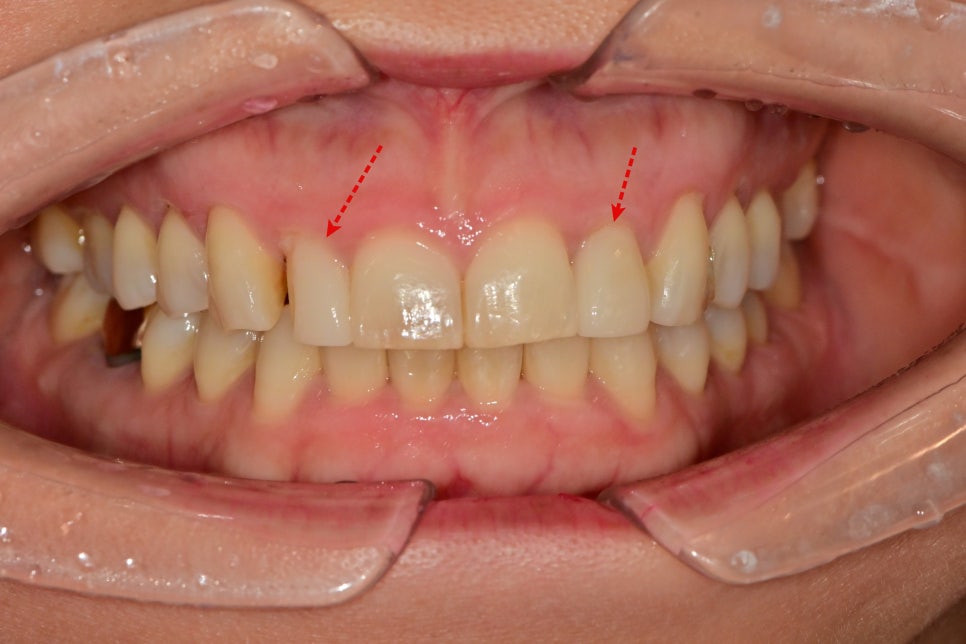

오래 사용하셨는데 파절된 부위를 보면

옆의 송곳니가 닳아져있는 것을 볼 수 있습니다.

송곳니가 닳게 되면서 그 옆의 치아에 장기간의

교합간섭이 일어나 일부가

파절이 된 것 같습니다.

가장 큰 대문니가 각이 져있는 형태이고 거기에

보철물을 맞추다 보니 디자인이 약간

막혀있고 답답한 느낌이 듭니다.